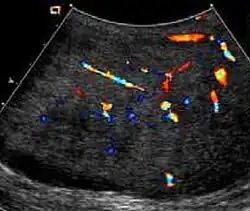

Fibrous pseudotumors, also known as fibromas are thought to be reactive, nonneoplastic lesions. They can occur at any age, about 50% of fibromas are associated with hydrocele, and 30% are associated with a history of trauma or inflammation (Akbar et al., 2003). Although the exact cause of this tumor is not completely understood, it is generally believed that these lesions represent a benign reactive proliferation of inflammatory and fibrous tissue, in response to chronic irritation. Sonographic evaluation generally shows one or more solid nodules arising from the tunica vaginalis, epididymis, spermatic cord and tunica albuginea [Fig. 18]. A hydrocele is frequently present too. The nodules may appear hypoechoic or hyperechoic, depending on the amount of collagen or fibroblast present. Acoustic shadowing may occur in the absence of calcification due to the dense collagen component of this tumor. With color Doppler sonography, a small to moderate amount of vascularity may be seen [Fig. 19].

Fig. 18. Fibrous pseudotumor. A homogeneous hypoechoic nodular lesion is seen attached to the tunica associated with minimal amount of hydrocele. -

Fig. 19. Fibrous pseudotumor. With color Doppler, a little vascular flow is seen in this fibrous pseudotumor.